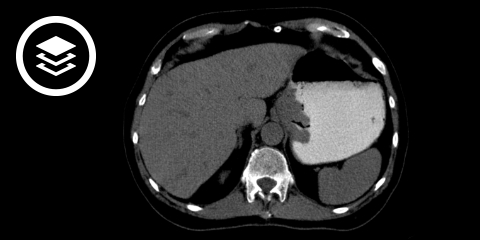

- CT-Thorax, -Abdomen und –Becken: bei Patienten mit kurativem Ansatz. Mit intravenösem Kontrastmittel und Magenfüllung mit oralem Kontrastmittel oder Wasser („Hydro-CT“). Suche nach Lungenmetastasen, Peritonealkarzinose, Fernmetastasen und lokoregionären Metastasen.

CT-Fallbeispiel

DICOM-Modelle können auf Mobilgeräten leider nicht angezeigt werden.

- Bildquelle DICOM-Viewer: Lucchesi, F. R., & Aredes, N. D. (2016). The Cancer Genome Atlas Stomach Adenocarcinoma Collection (TCGA-STAD) (Version 3). The Cancer Imaging Archive